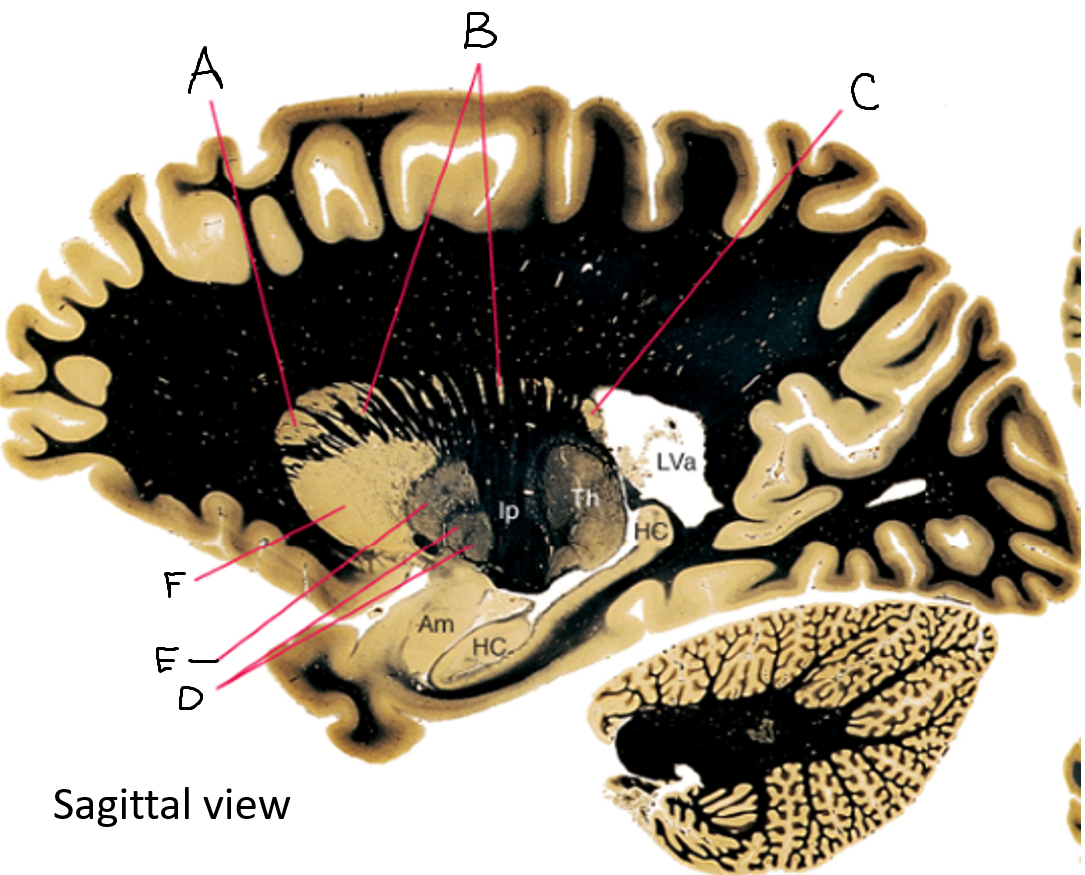

A

corpus callosum

B

cerebral cortex

C

caudate

D

putamen

F

anterior commissure

G

amygdala

H

optic chiasm

I

basal forebrain nuclei

K

internal capsule